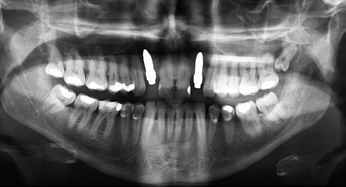

Der klinische Befund zeigte eine definitive Versorgung auf 12 und eine temporäre Versorgung auf 22. Dahingegen lag bei der Implantatversorgung in regio 22 der Verdacht auf eine partielle Fibro-Osseointegration vor (Abb. 1 und 2) [9,10].